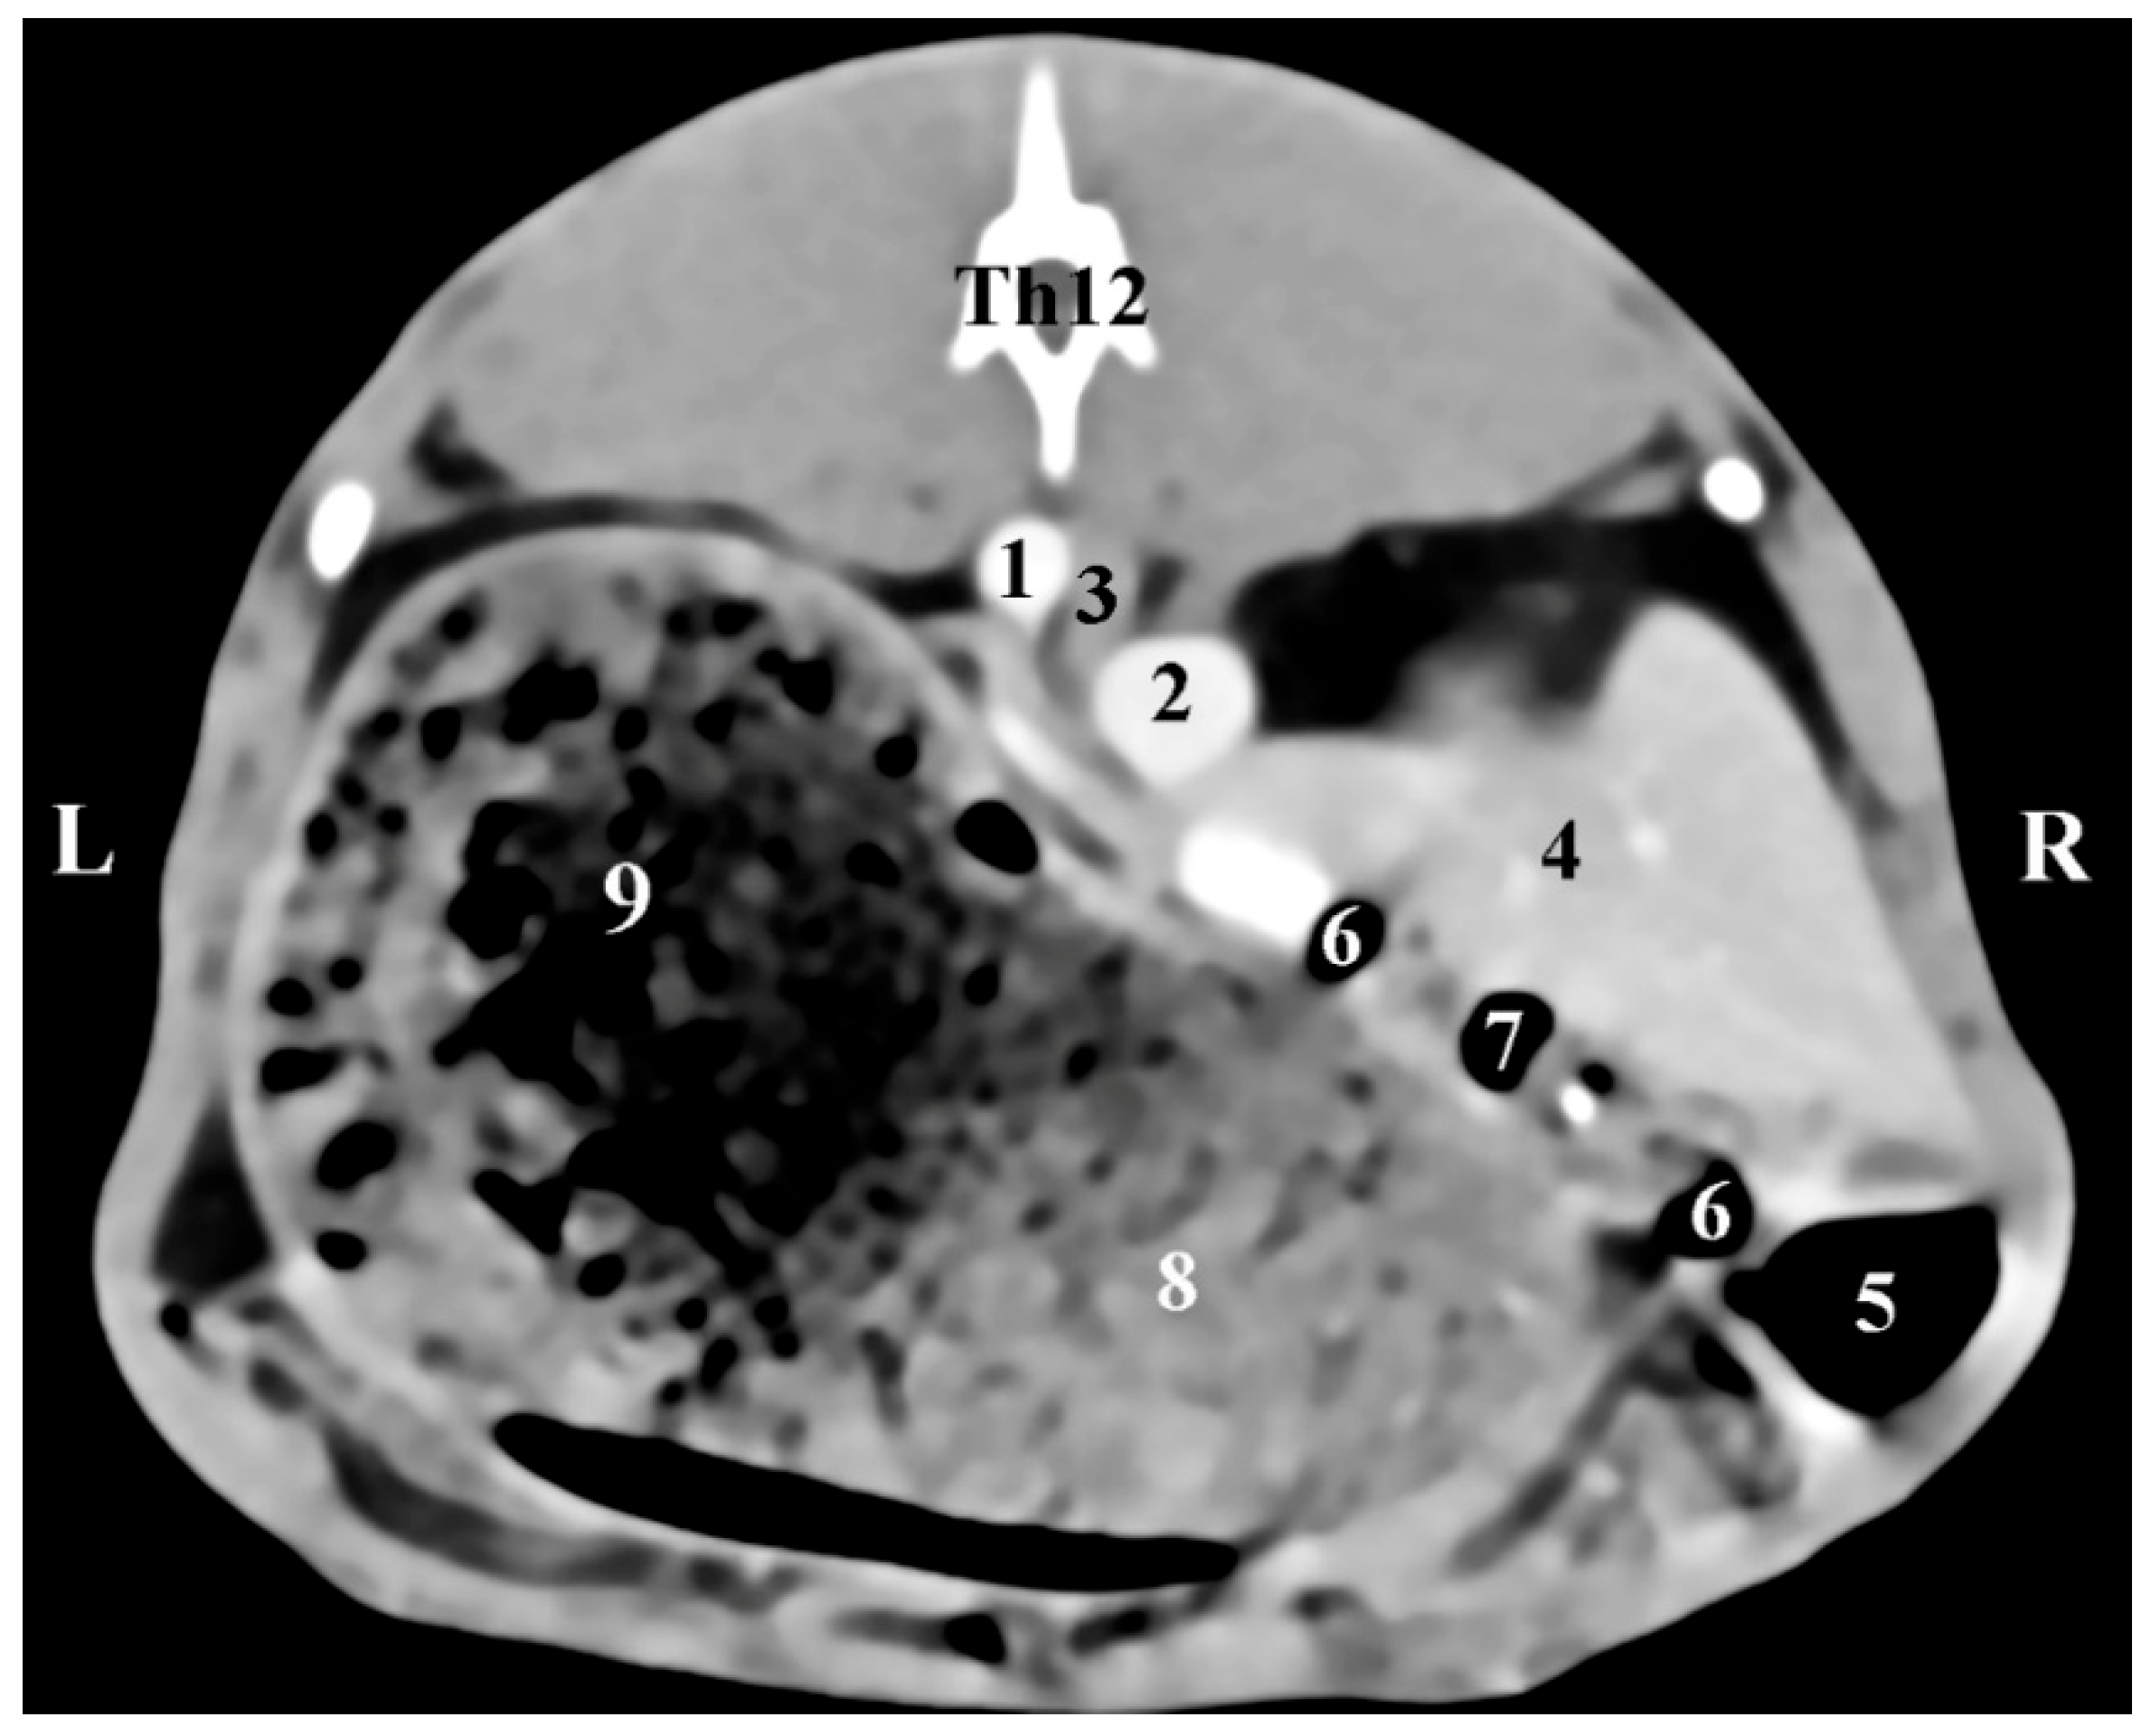

The dorsal (coronal) post-contrast anatomical CT study of regio abdominis through the dorsal plane 30 mm ventrally to the spine showed the elliptical shape of the homogeneous and sharply delineated image of the right adrenal gland. The gl. adrenalis dextra was located in the regio abdominis lateralis dextra of the regio abdominis media. The gland was retroperitoneally located, medially in contact with the v. cava caudalis, and was observed craniomedially to the hyperattenuated borders of the right kidney and caudally to the Proc. caudatus of the caudate liver lobe, with which it was in anatomical contact. The border between them was defined by hypoattenuated contours of the impression of the right adrenal on the proc. caudatus. Dorsally, the gland was in contact with the m. longissimus (Figure 5).

Figure 5. Dorsal (coronal) CT post-contrast anatomical study of the rabbit abdomen (at the plane 30 mm ventral from the vertebral column). CR—cranial; CD—caudal; R—right; L—left. (black star) right adrenal gland; (1) Right kidney; (2) left kidney; (3) right adrenal gland; (4) liver; (5) fundus et corpus ventriculi; (6) v. cava caudalis; (7) aorta abdominalis; (8) longissimus muscle; (9) impression of the right adrenal gland; (*) proc. caudatus.